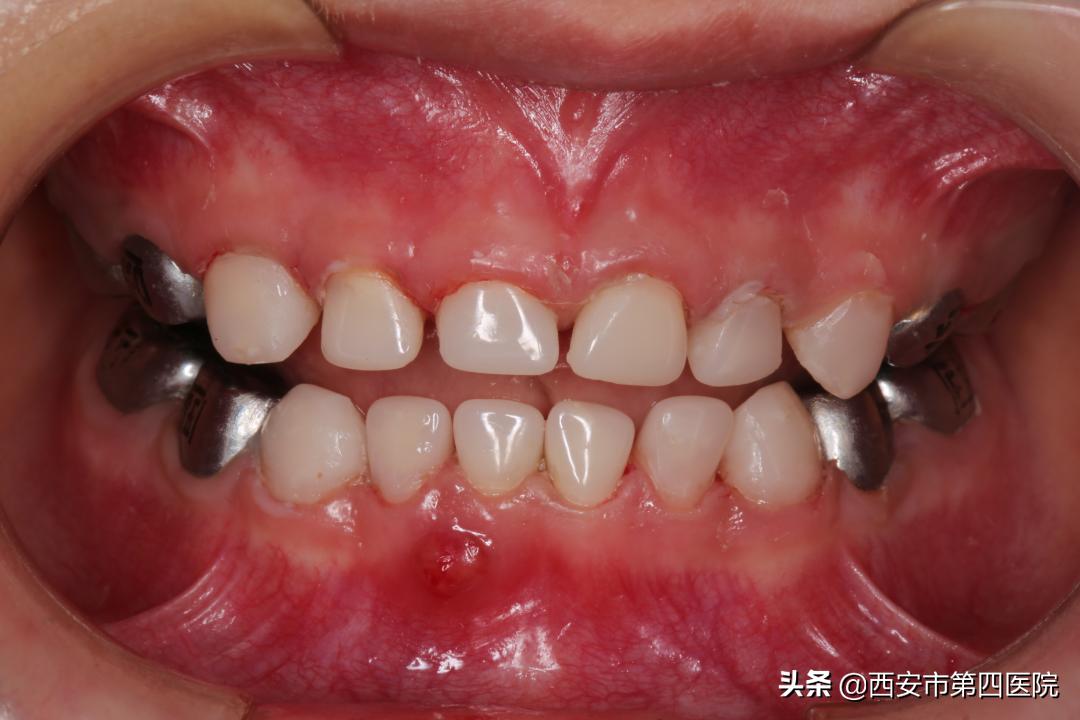

盖髓术、根管治疗术、预成金属冠修复、乳牙拔除、间隙保持器印模制取……

每个步骤都有条不紊地进行,麻醉团队全程监护,在整个手术团队的通力配合下,上午11时整,手术顺利结束,全程耗时约2小时。

(左图为术前,右图为术后)

看到孩子术后恢复良好,口腔内多种疾病一次性治疗完成,家长非常满意。